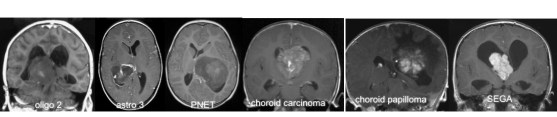

les différentes tumeurs du ventricule latéral

l’astrocytome à cellules géantes sous-épendymaire (Bourneville)

- le papillome du plexus choroïde

- le carcinome du plexus choroïde

- les gliomes de haut grade

- les gliomes de bas grade

- l’épendymome (qui contrairement à ce qu’on pense intuitivement, est le plus souvent extra-ventriculaire)